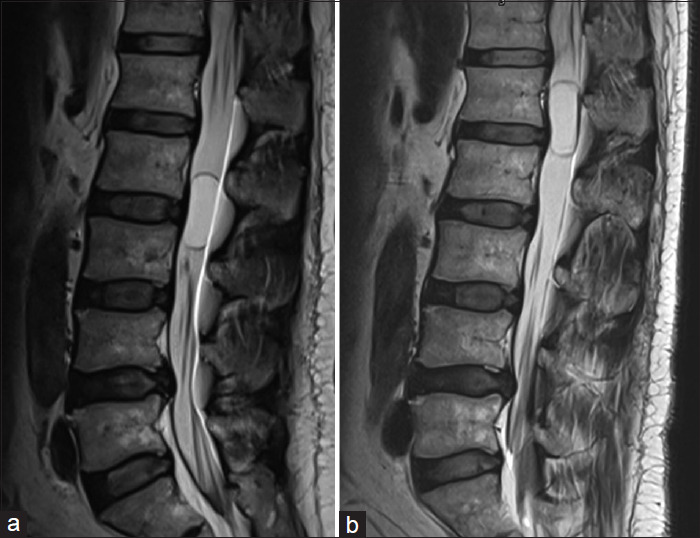

移动神经鞘瘤或雪旺细胞瘤是罕见的,但其在椎管内迁移的能力使诊断和治疗复杂化。我们报告两例下胸椎和腰椎的移动神经鞘瘤,均表现为间歇性腰痛和腿部疼痛以及腿部麻木。核磁共振成像显示囊性肿块随着时间的推移而改变位置,最终引起破坏性疼痛,促使手术干预。术后结果良好,突出了在术前计划中考虑肿瘤移动性的重要性。移动神经鞘瘤目前的诊断和手术挑战。认识到肿瘤移动的潜力对于制定有效的治疗策略至关重要,因为它影响临床表现和手术方法。

Mobile schwannomas, or schwann cell tumors, are rare, but their ability to migrate within the spinal canal complicates diagnosis and treatment. We report two cases of mobile schwannomas in the lower thoracic and lumbar spine, both presenting with intermittent low back and leg pain and leg numbness. MRIs revealed cystic masses that shifted positions over time, eventually causing disruptive pain that prompted surgical intervention. Postoperative outcomes were favorable, highlighting the importance of considering tumor mobility in preoperative planning. Mobile schwannomas present diagnostic and surgical challenges. Recognizing the potential for tumor mobility is crucial in developing effective treatment strategies, as it impacts clinical presentation and surgical approach.